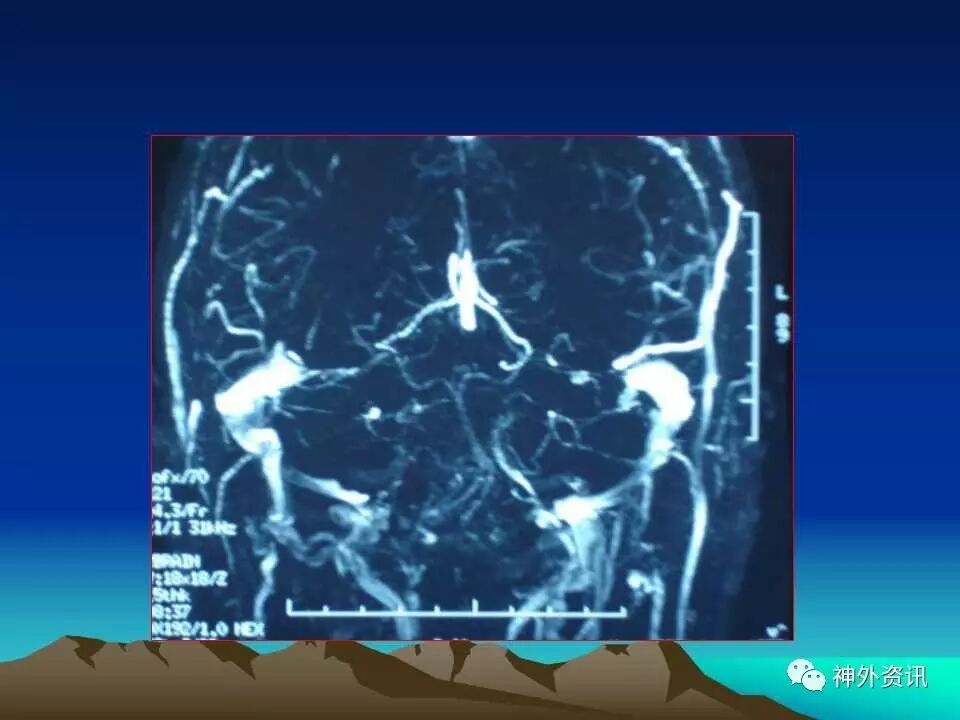

“枕下极外侧髁上入路处理颈静脉孔区肿瘤:

75例分析和总结”精彩讲课视频